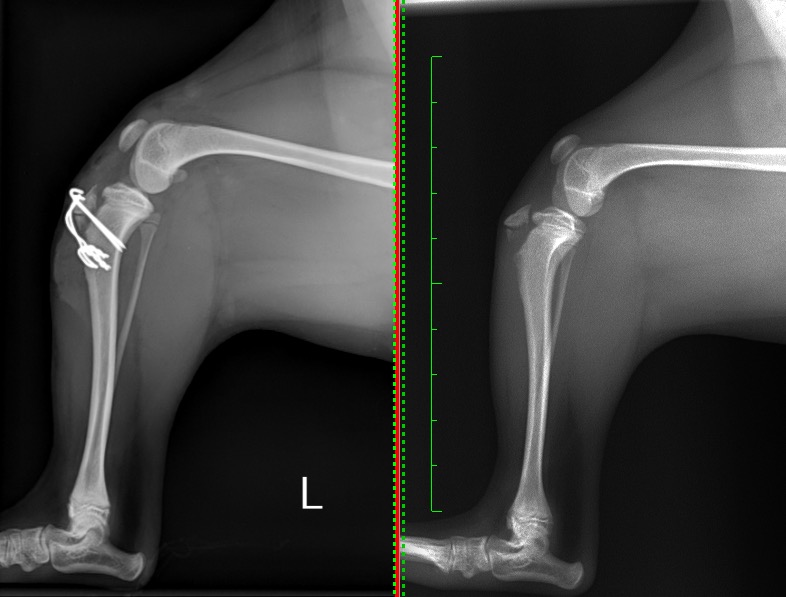

右が手術前、左が整復手術後になります。

上方変位している脛骨粗面を本来の位置に引っ張り戻した後、金属製のピンを2本挿入し固定しました。

この時点で十分な整復を得ることができましたが、靭帯や筋肉による上に引っ張る強い力によってピンが抜けてきてしまうリスクを軽減させるため、整形外科ワイヤーを使いピンを圧着させる手技(テンションバンドワイヤー法)を追加で行いました。

術後の経過はとても良く、膝関節の痛みや腫れもなく元気に足を使えるようになりました。